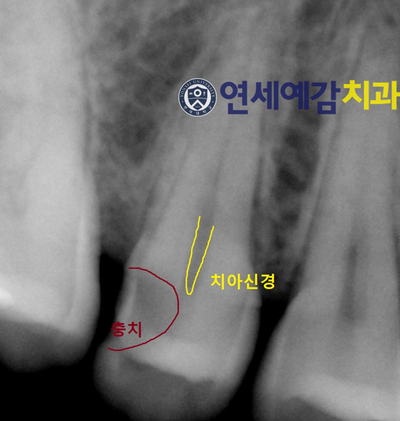

5년 전의 방사선 사진을 달라고 아직 그 병원에 있는 동생에게 부탁해서

이번에 약소한 생일선물로 받았습니다... tmi..

충치의 부위와 치아 신경이 근접해서

신경치료를 해야한다고 예상할 수 있는 상황이었습니다.

그리고 방사선사진상의 왜곡 때문에 사진상에 저렇게 보일지라도

실제로 치아 충치를 제거하다보면

방사선상에서 보이는 것보다 훨씬 깊고 심한 경우가 많습니다.